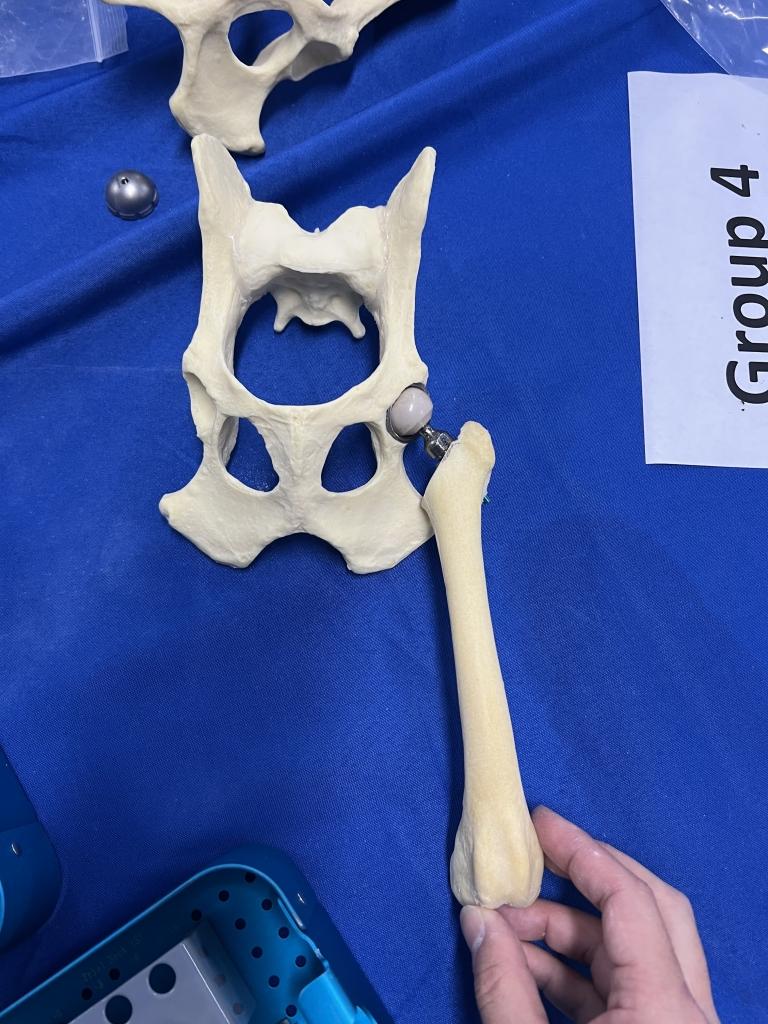

大腿骨ステムのサイズをシュミレーションしています

実際の骨模型を使用した人工股関節の設置トレーニング